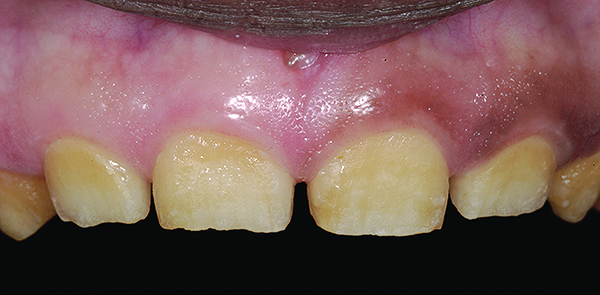

Figure 15. Final anterior tooth preparations.

Figure 15

It was decided to follow the latter approach of making the anterior finals first. The approved provisional restorations were removed by cutting them back with burs of a known diameter so that a clearance of 0.5 mm to 1 mm was accomplished on the labial surface and 1.5 mm on the incisal. As the depth cuts were made on the anterior provisionals, it was found that the underlying tooth structure hardly needed any preparation at all. Once all provisional material was stripped off, a medium abrasive disc (Super-Snap®, Shofu, www.shofu.com) was used to smooth out the tooth surfaces (Figure 15). Usually, a chamfer margin is prepared conventionally in such restorative designs; however, since there was no enamel present in the cervical areas, the authors preferred to have a negligible-thickness, knife-edged margin placed equigingivally. The putty index from the provisionals was cut back and used to verify that sufficient clearance was present for the final restorations. The restorations were designed to replace the enamel layer on anterior teeth and also provide a definite CEJ.